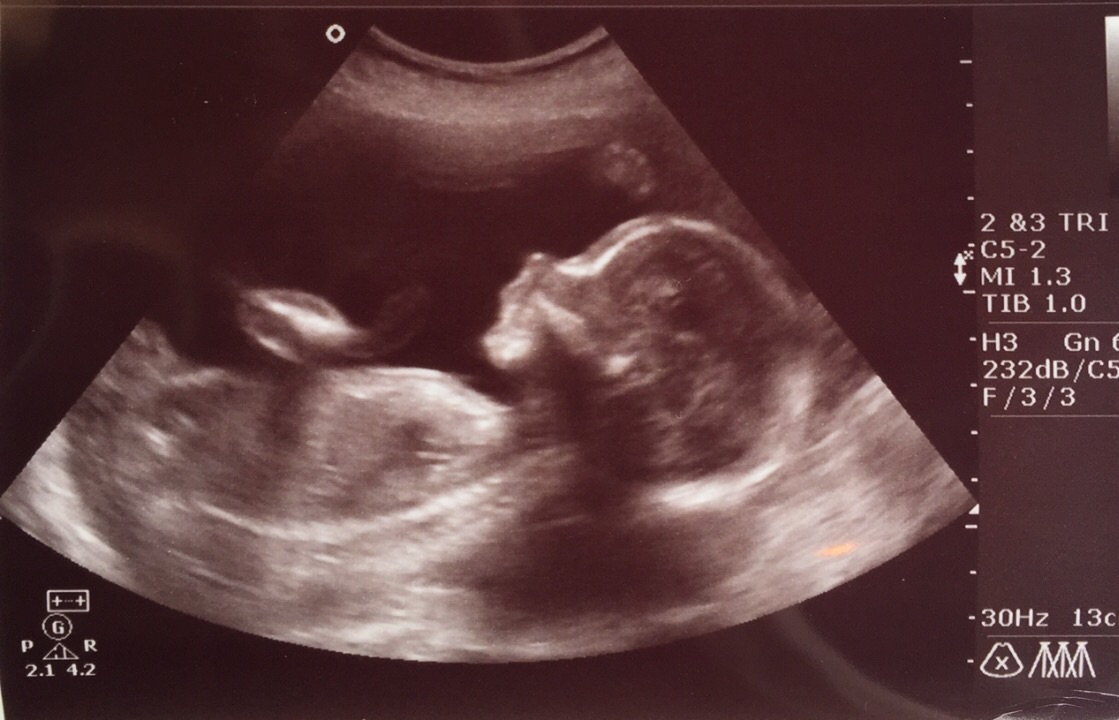

Well lol went to two different gynecologist, the first one wasn't even sure just said it was a Boy,come to find out with the 2nd gynecologist she said it was 100% a girl. Her name is going to be Svetlana Sain Due Date 11/08/15

Her name is going to be Svetlana Sain

Due Date 11/08/15

Esther Sophia is due nov-2nd